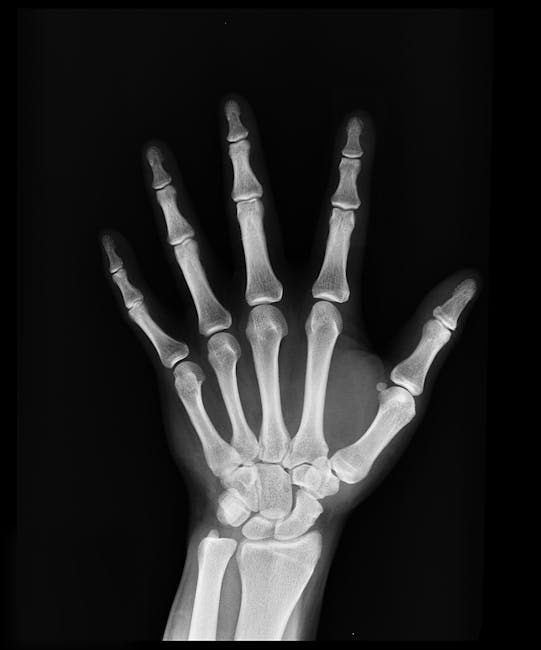

What is Appendicular Skeleton?

The appendicular skeleton comprises the bones of the limbs and their corresponding girdles, facilitating movement and interaction with the environment. It plays a vital role in locomotion and manipulation of objects.

The appendicular skeleton includes the pectoral girdle, upper limbs, pelvic girdle, and lower limbs. Each region has specialized bones adapted for specific functions such as grasping, lifting, or walking.

The appendicular skeleton provides the mechanical basis for voluntary movement, enabling activities like walking, running, and grasping. Joints within this skeleton exhibit a wide range of motions, from hinge-like bending to rotational twisting.

Upper limb bones, such as the humerus, radius, and ulna, work together to allow precise hand positioning and tool use. This dexterity is critical for tasks ranging from writing to complex manual labor.